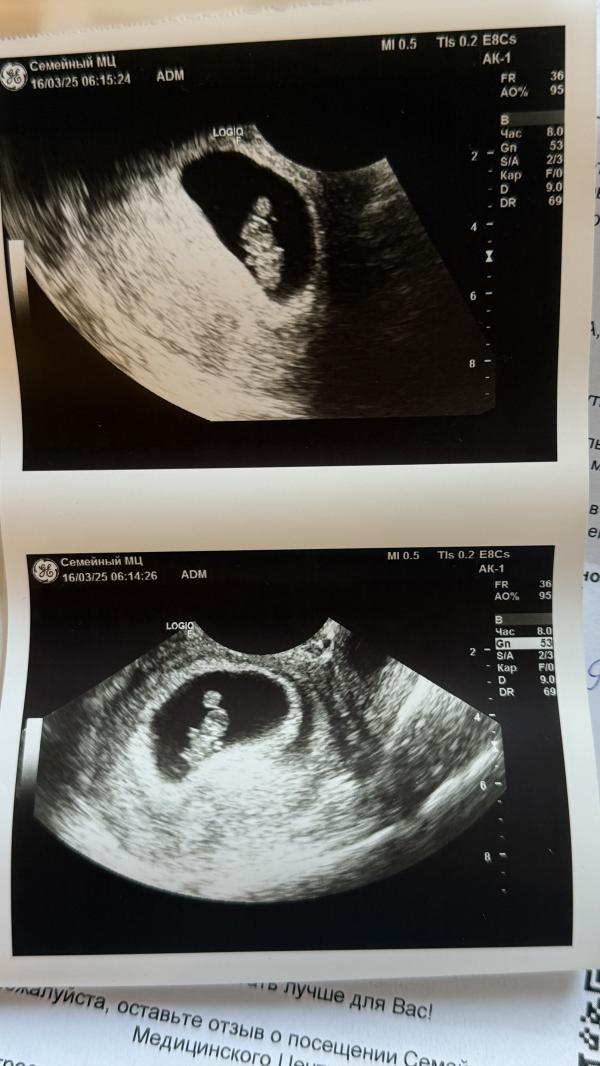

post image